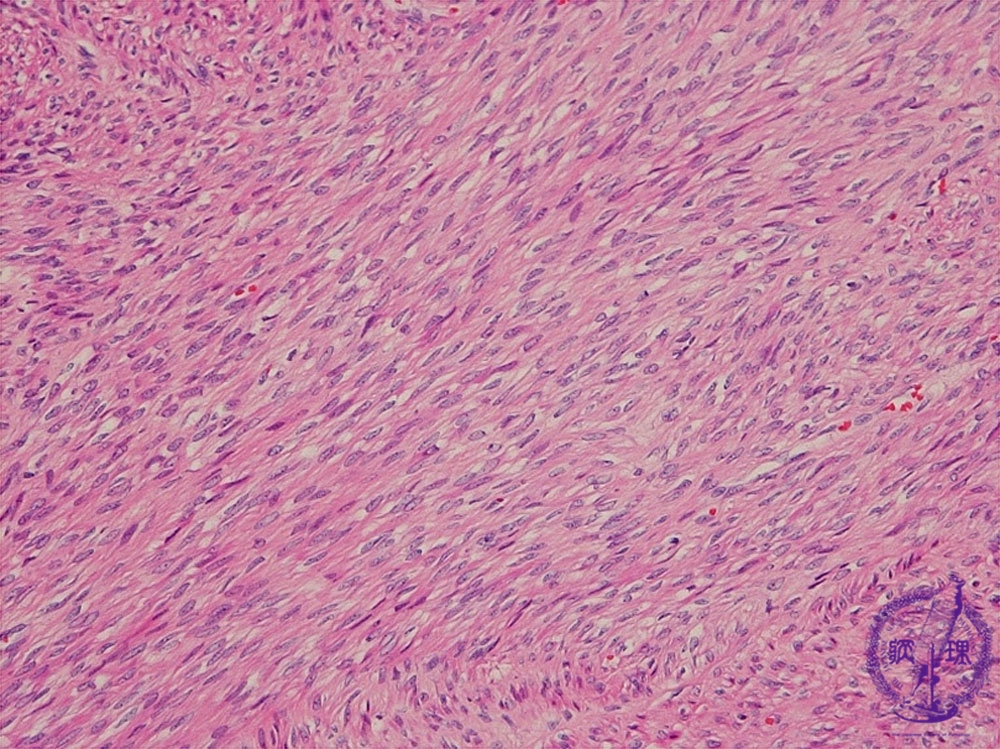

Histology (HE stain, intermediate power): Smooth muscle-like spindle tumor cells formed in an intricate fascicle pattern.